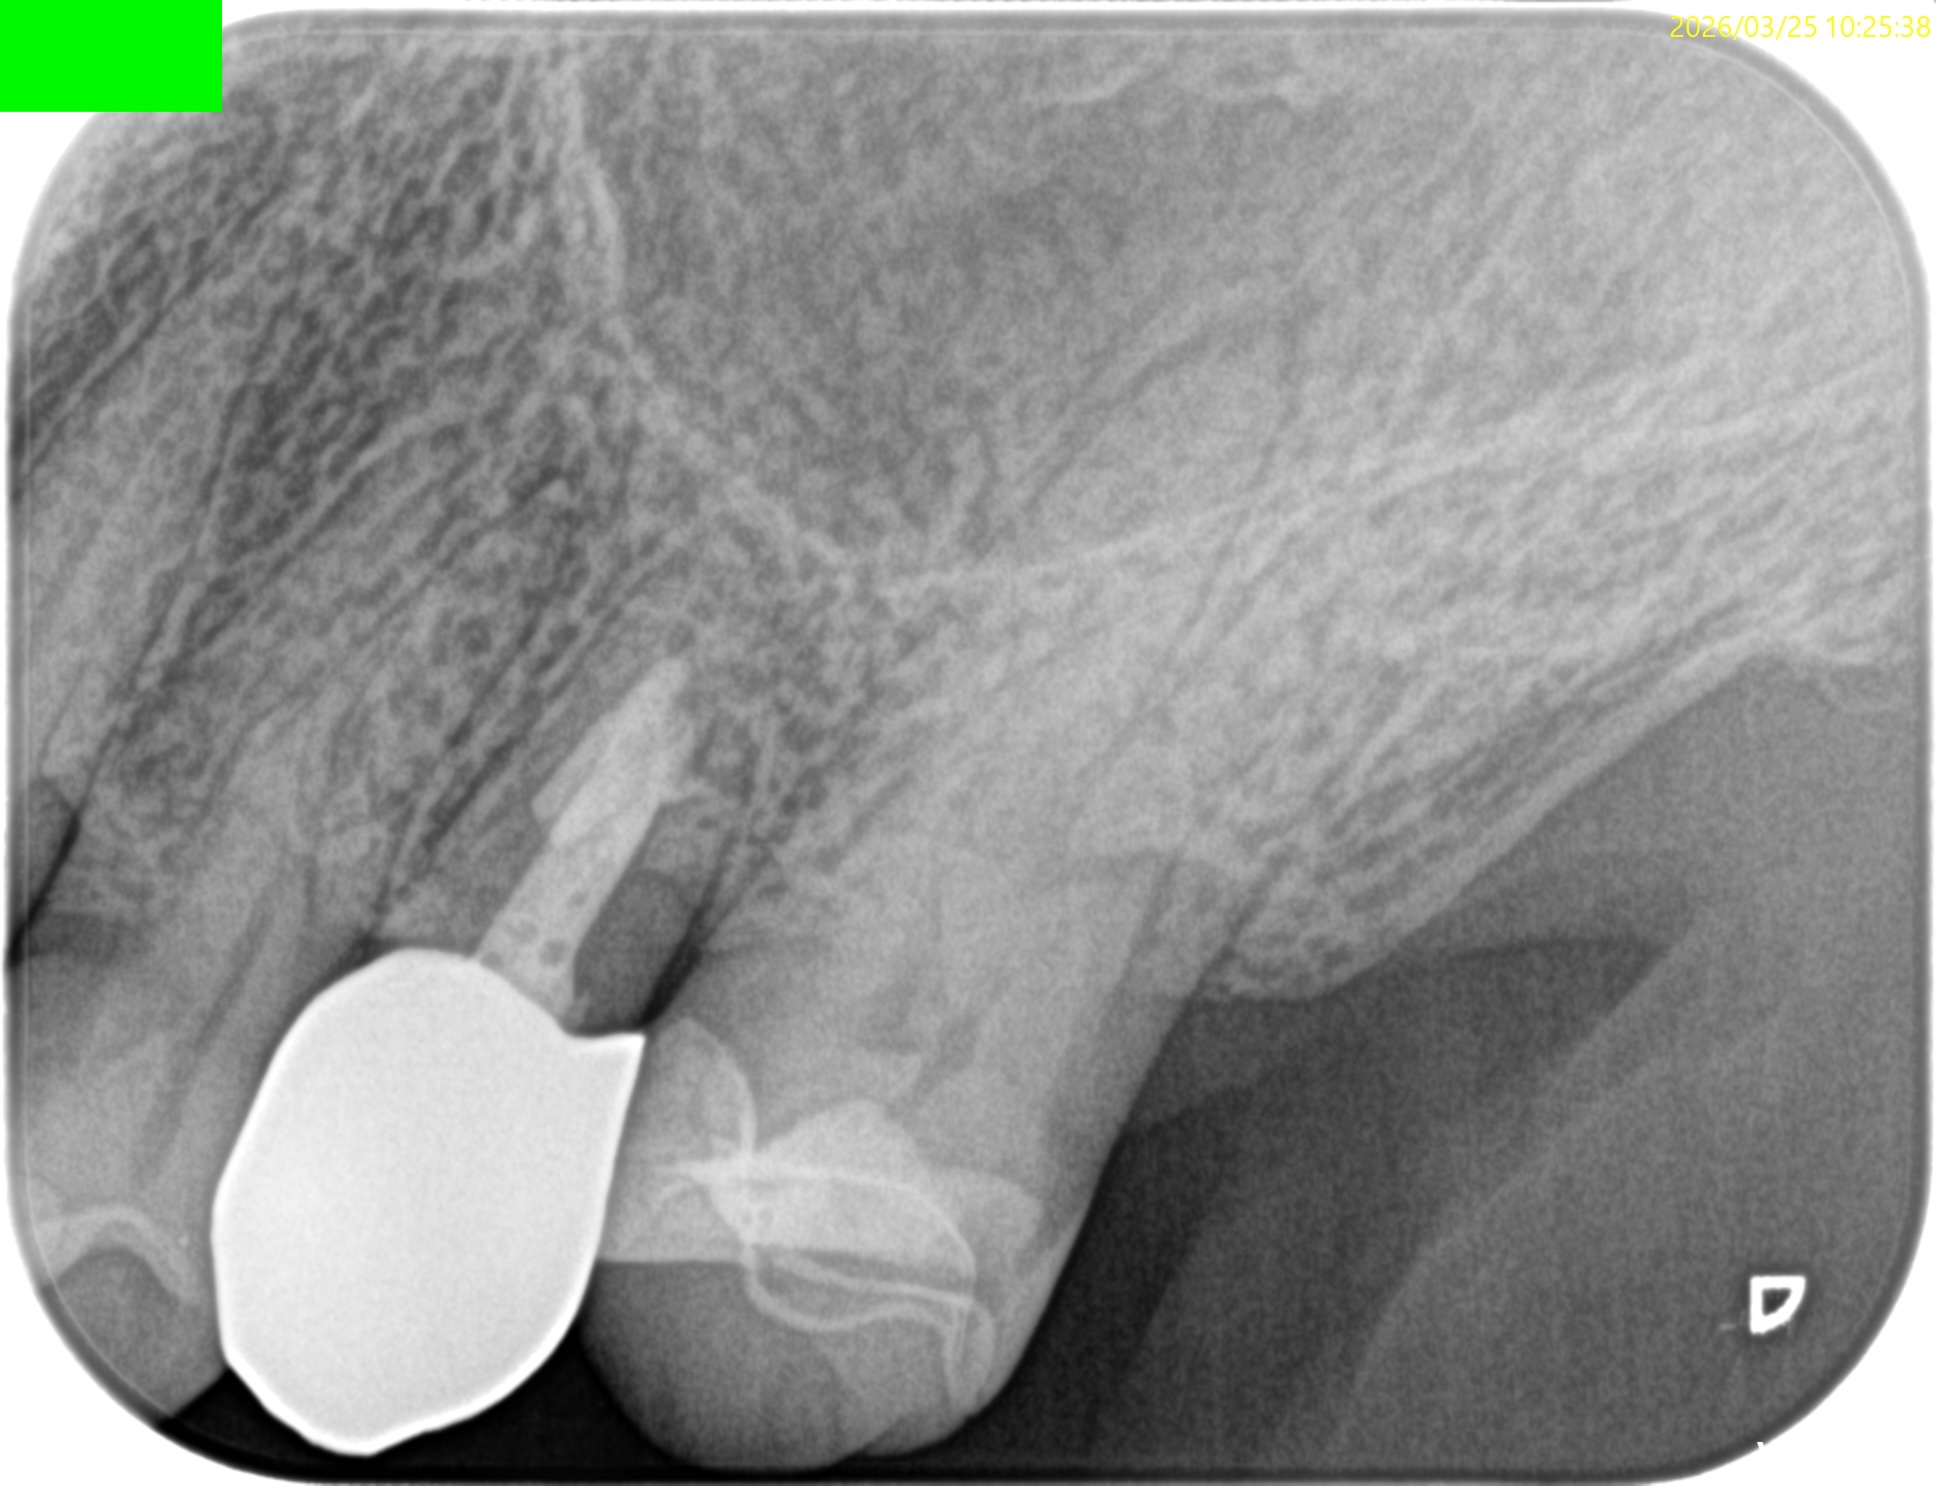

#13 Apicoectomy 1yr recall(2026.3.25)

1年前と比較してみた。

根尖病変は消失し、外科治療に関わる骨欠損も完治した。この状態ならセラミックに変えてもいいだろうが、術前の状態では無理である。